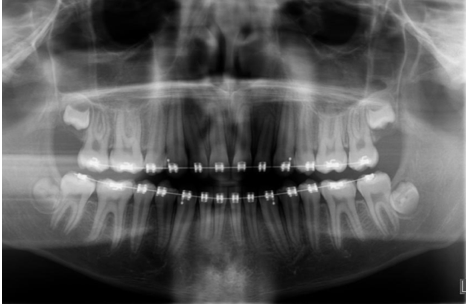

Name this type of radiograph

Panoramic